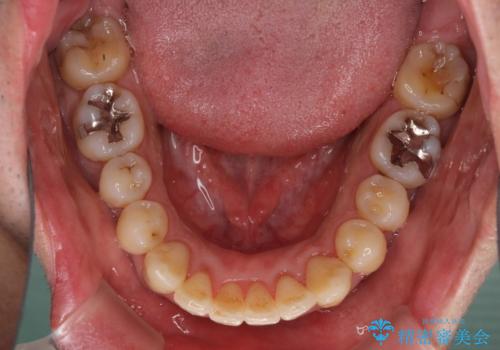

インビザラインは1日22時間を目標にマウスピースを装着することで歯列を改善するものです。

そのため、上下の歯が接触することはほとんどなく、マウスピースを介した咬合において歯列矯正が進んでいきます。

この方は元々骨格的な偏位が大きかったためか、治療中に下顎骨が上顎骨よりも右外側に誘導されて、右側の奥歯が全く咬合しない状態が続いてしまいました。

最終的にはゴムかけなどを活用して改善することができましたが、4年近い治療期間を要することとなりました。